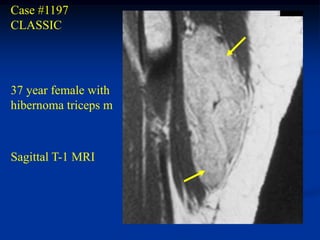

Case #1197

CLASSIC

37 year female with

hibernoma triceps m

Sagittal T-1 MRI